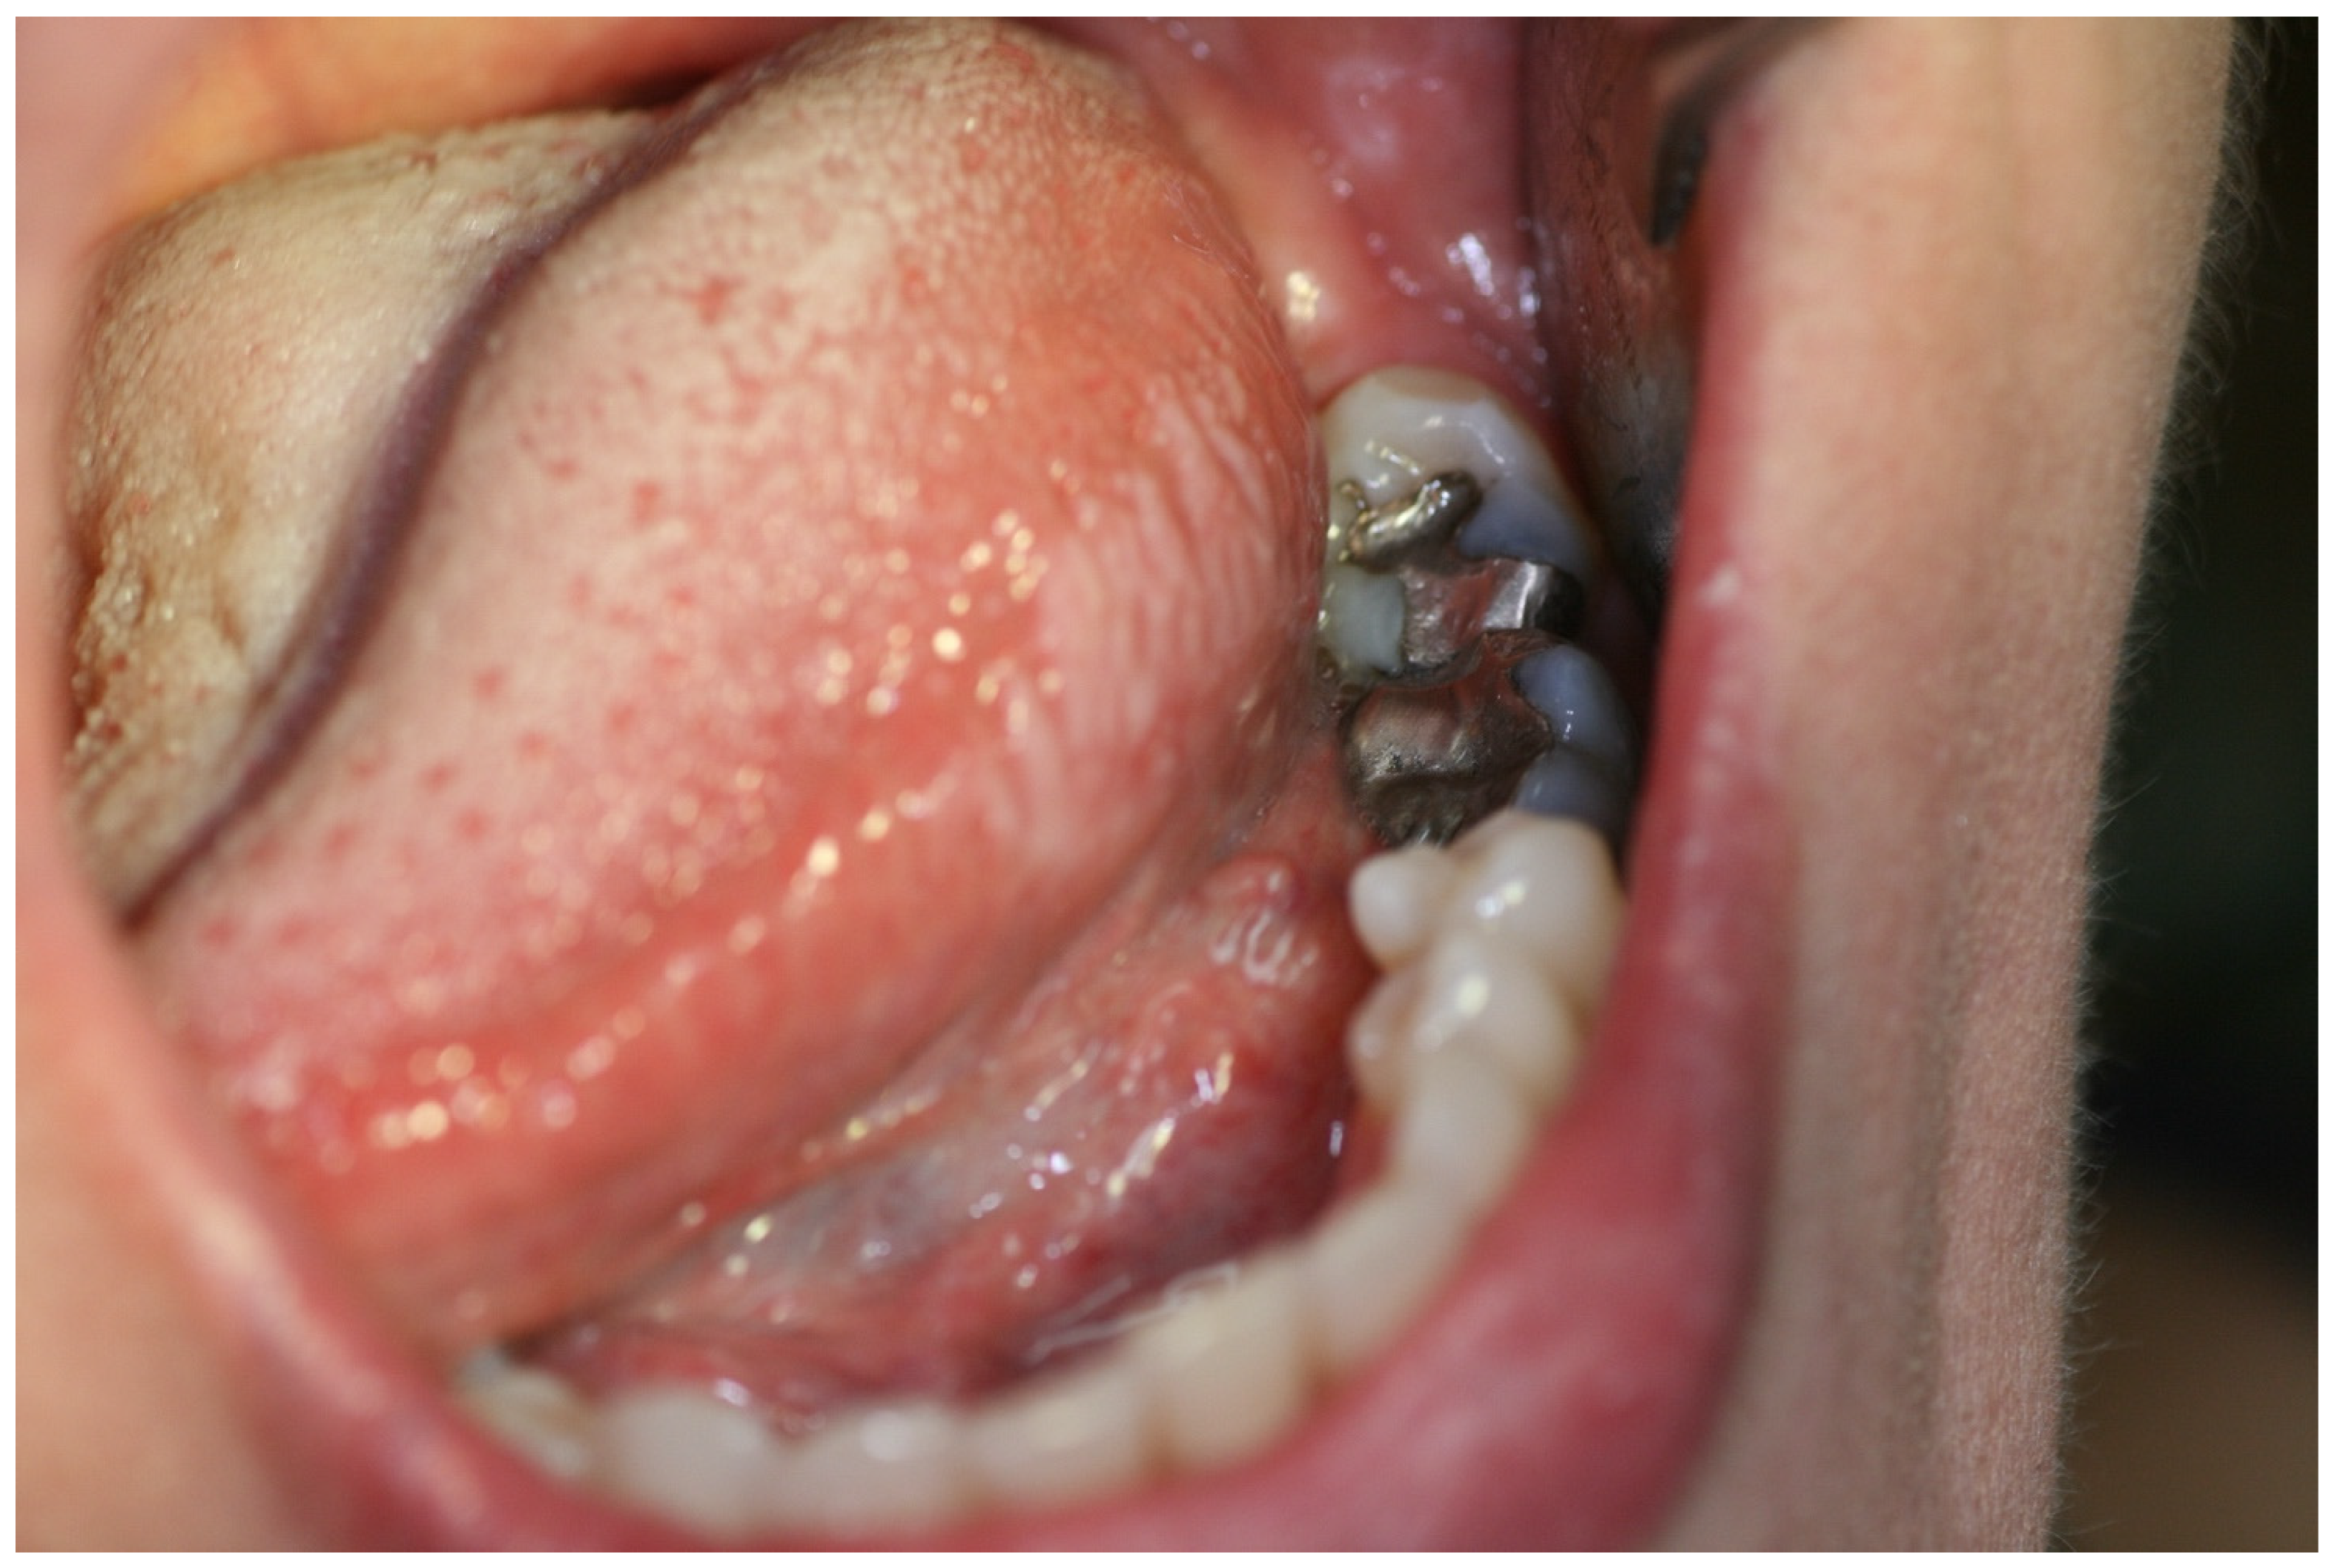

2. Case Report